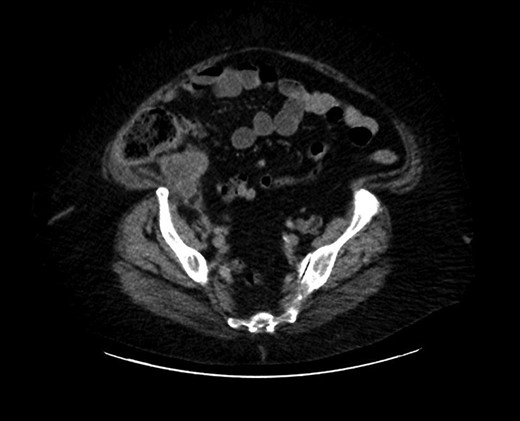

CT scan of the abdomen revealed stable soft tissue focus and adjacent rim of enhancing low-density collection along the posteromedial and posterior aspects of the cecum in the right lower abdomen (Fig. 2). Suggestive of the possibility of chronic infectious or neoplastic etiologies of appendicular origin. The appendix was not visualized as a separate structure. Comparison of the previous CT excluded worsening of the intra-abdominal or intra-pelvic process. Upon discussion with medical and surgical teams, reproduction of symptoms and CT evidence, aided the direction for surgical intervention. On the second day of hospital admission, surgical laparoscopy located the terminal ileum with adhesions from the sidewall. The findings included perforated viscus and mass at the appendicular base. With this appearance, a direct intervention was impossible, we proceeded with hand-assisted partial cecectomy, appendectomy and removed the entire mass.

Marked appendiceal wall swelling and intraluminal filling defect of contrast medium over appendix noted in the coronal CT-image.